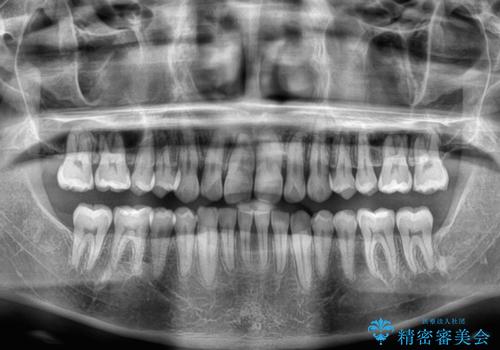

上顎歯列を遠心移動させたことで、前歯の叢生が解消されても前歯が前突することなく、左右ともに理想的な咬み合わせを達成することができました。